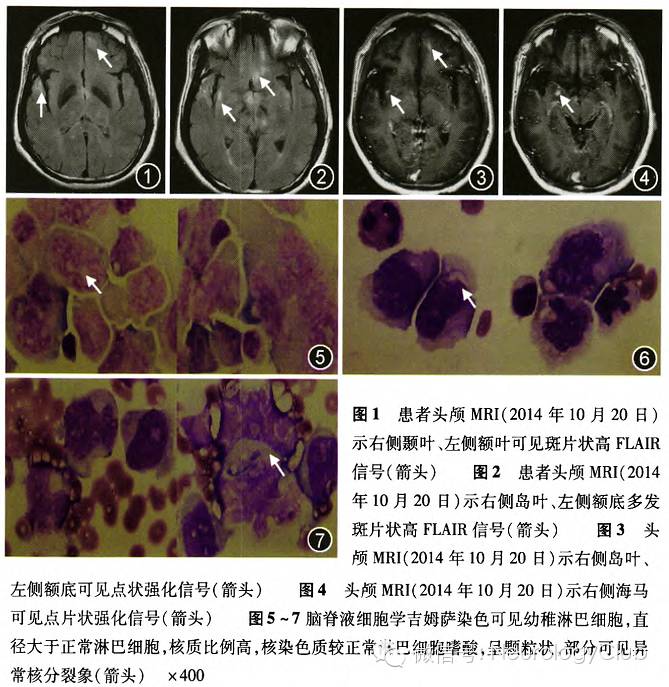

患者男性,55岁。主因“反应迟钝20余天,加重伴意识不清4d”于2014年10月17日入院。患者于20余天前无明显诱因出现反应迟钝,与人交流减少,能认识家人,生活基本自理,就诊于当地医院,行脑电图检查示全脑广泛明显异常,诊断为“病毒性脑炎”,给予抗病毒治疗(具体治疗不详)后,症状无明显缓解。于4d前腹泻1次,逐渐出现意识不清,不能认识家人,言语及进食困难。既往史、个人史及家族史无特殊。入院后体检:体温37.9℃,心率82次/min,呼吸18次/min,血压122/77mmHg(1mmHg=0.133kPa)。神经内科体检:意识模糊,体检欠合作,对光反应灵敏,脑神经体检阴性,四肢可见自主活动,四肢肌张力、腱反射正常,双侧巴宾斯基征未引出,脑膜刺激征阴性。入院后查血常规、生化全项、凝血常规、大小便常规未见明显异常,术前四项(乙型肝炎、丙型肝炎、梅毒螺旋体、获得性免疫缺陷综合征)、垂体激素六项、甲状腺激素、血皮质醇(晨起8:00)、血维生素(维生素B12、叶酸)、肿瘤标志物检查未见异常。头MRI+MRA(2014年10月20日)示脑内多发异常长T2高FLAIR信号,强化后部分信号可见强化(图1-4),MRA未见异常。经患者家属知情同意,行腰椎穿刺术,示颅内压110mmH2O(1mmH2O=0.0098kPa),脑脊液常规:总细胞50×10^6/L,白细胞2×10^6/L,脑脊液生化:氯化物125mmol/L(正常值118-132mmol/L)。葡萄糖1.4mmol/L(正常值2.5-4.5mmol/L),白蛋白1.02g/L正常值(0.15-0.45g/L)。脑脊液细胞学:光镜下可见幼稚细胞(图5-7)。脑脊液流式细胞学示:脑脊液中发现部分大细胞,表达B淋巴细胞表型。查腹部超声未见异常,骨髓穿刺示粒系、红系细胞成熟正常,未见幼稚细胞。诊断为PCNSL(弥漫性大B细胞淋巴瘤可能性大)。

本患者以认知及意识障碍起病,神经系统查体无明显定位体征,提示为广泛皮质及皮质下白质病变,腰椎穿刺脑脊液细胞学发现原始幼稚淋巴细胞,直径大于正常淋巴细胞,核质比例高,核大饱满,呈不规则型,核染色质较正常淋巴细胞嗜酸,排列疏松,呈颗粒状,部分可见异常核分裂象。脑脊液流式细胞学检查脑脊液中发现部分大细胞,表达B淋巴细胞表型,其中CD19阳性的B淋巴细胞占63.3%,提示存在异常B细胞克隆。体格检查及腹部超声未发现体表及腹腔淋巴结肿大,骨髓穿刺骨髓像未发现幼稚细胞。因此诊断为PCNSL。